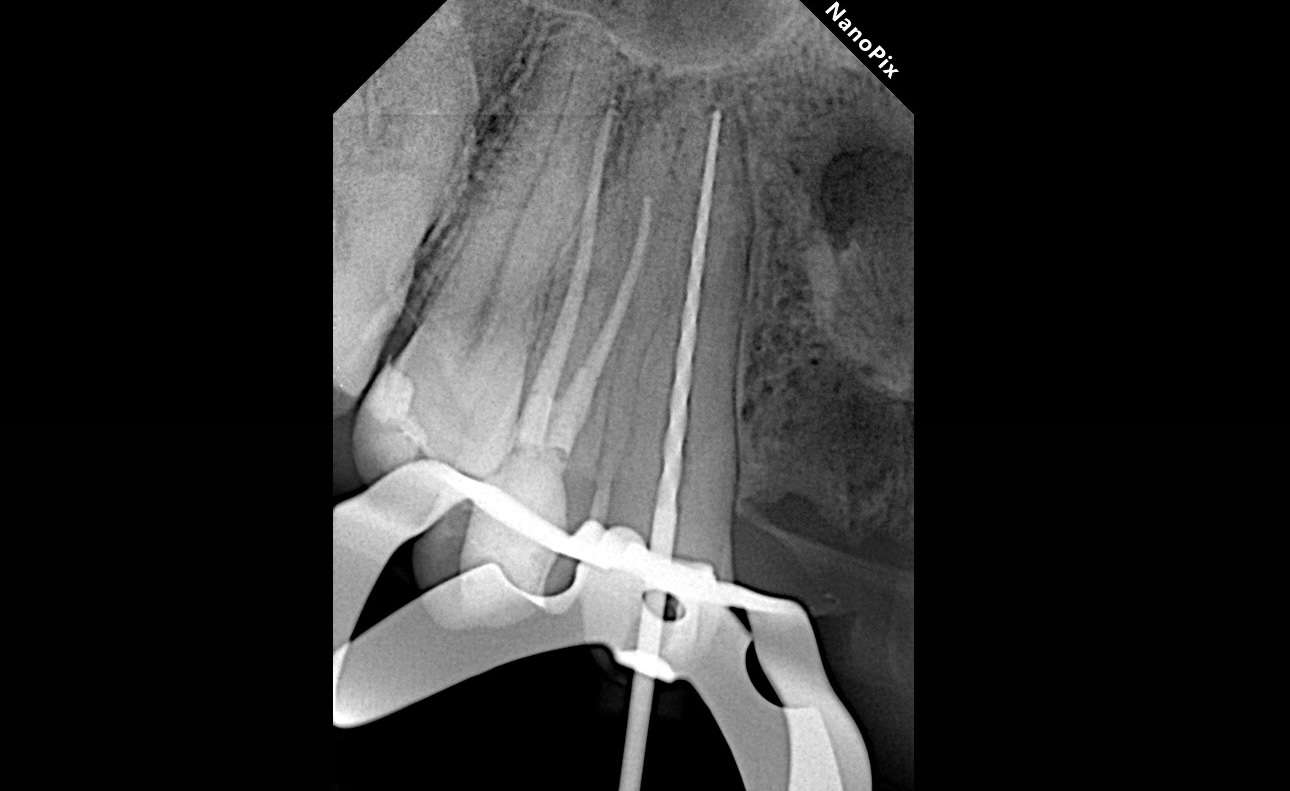

1.3 Хронический апикальный периодонтит.

Длина корневого канала 24 мм.

Дезобтурация Sani retreatment. Важно работать от корональной трети, постепенно двигаясь в апикальном направлении. Не стремиться сразу пройти на всю длину канала.

Инструментация Soco SC до 45/04. Финишный инструмент до чистых опилок на кончике файла.